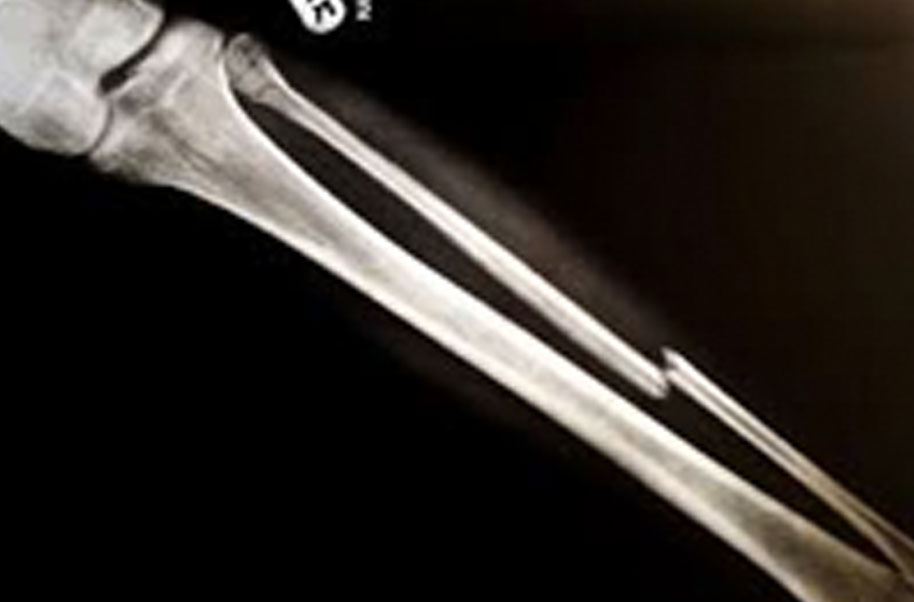

Phalanx (Broken Bone)

A complete or partial break in a bone.